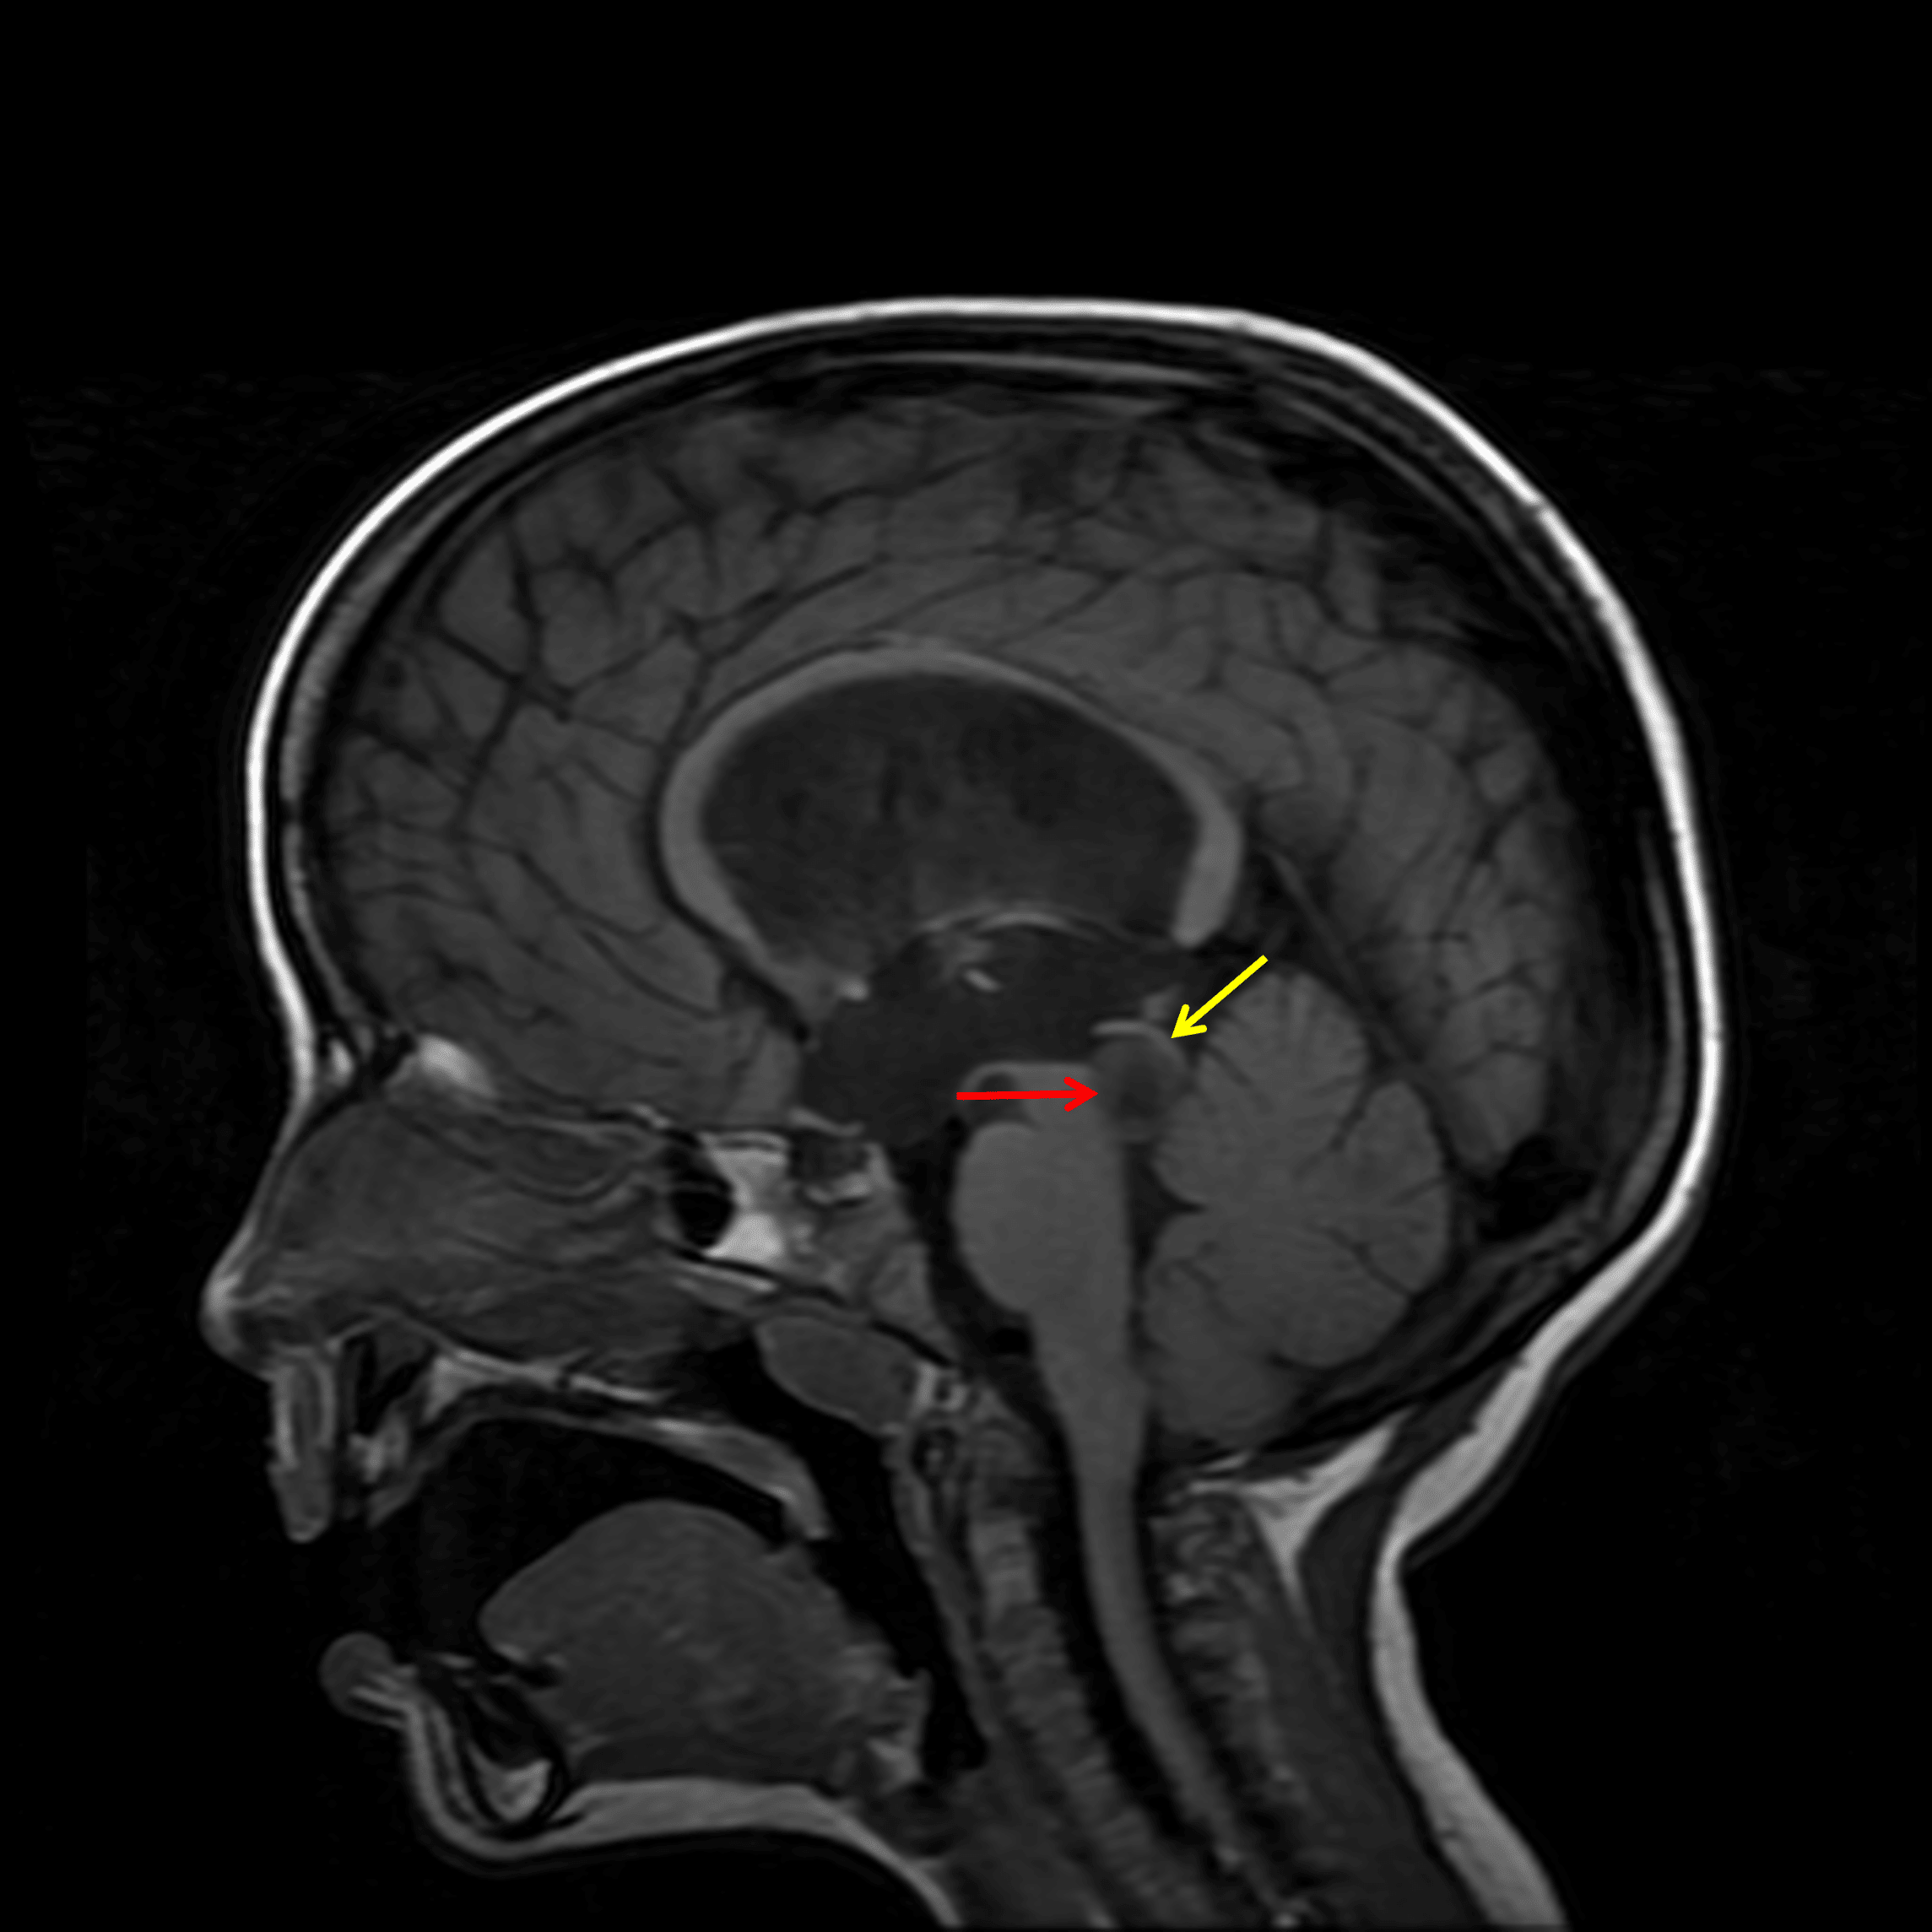

- T1 hypointense, T2/FLAIR hyperintense lesion in the right eccentric tectum measuring 1.5 x 1 x 1.5 cm

- Associated mass effect on the cerebral aqueduct with resultant obstructive hydrocephalus and mild subependymal edema

T1 hypointense tectal mass (red arrow) with associated obstructive hydrocephalus at the level of the cerebral aqueduct. A rim of normal parenchyma along its superior margin (yellow arrow) helps exclude a pineal origin of this particular mass.

Tectal glioma